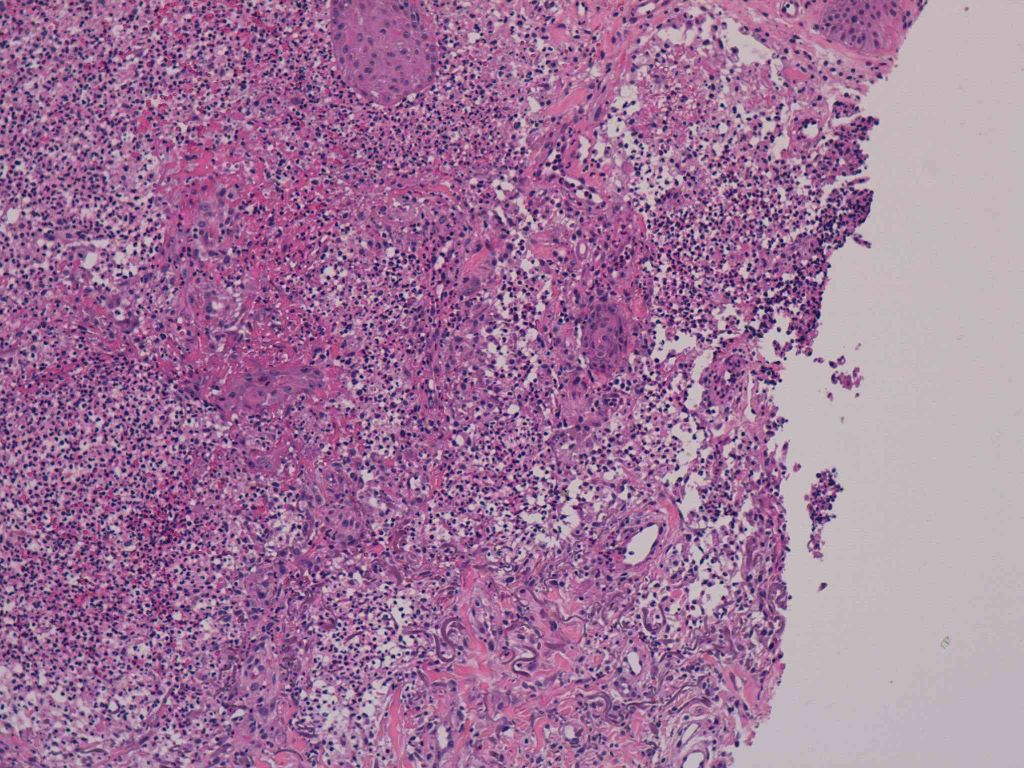

8 -- image_2011y09m14d_06h58m31s.jpg